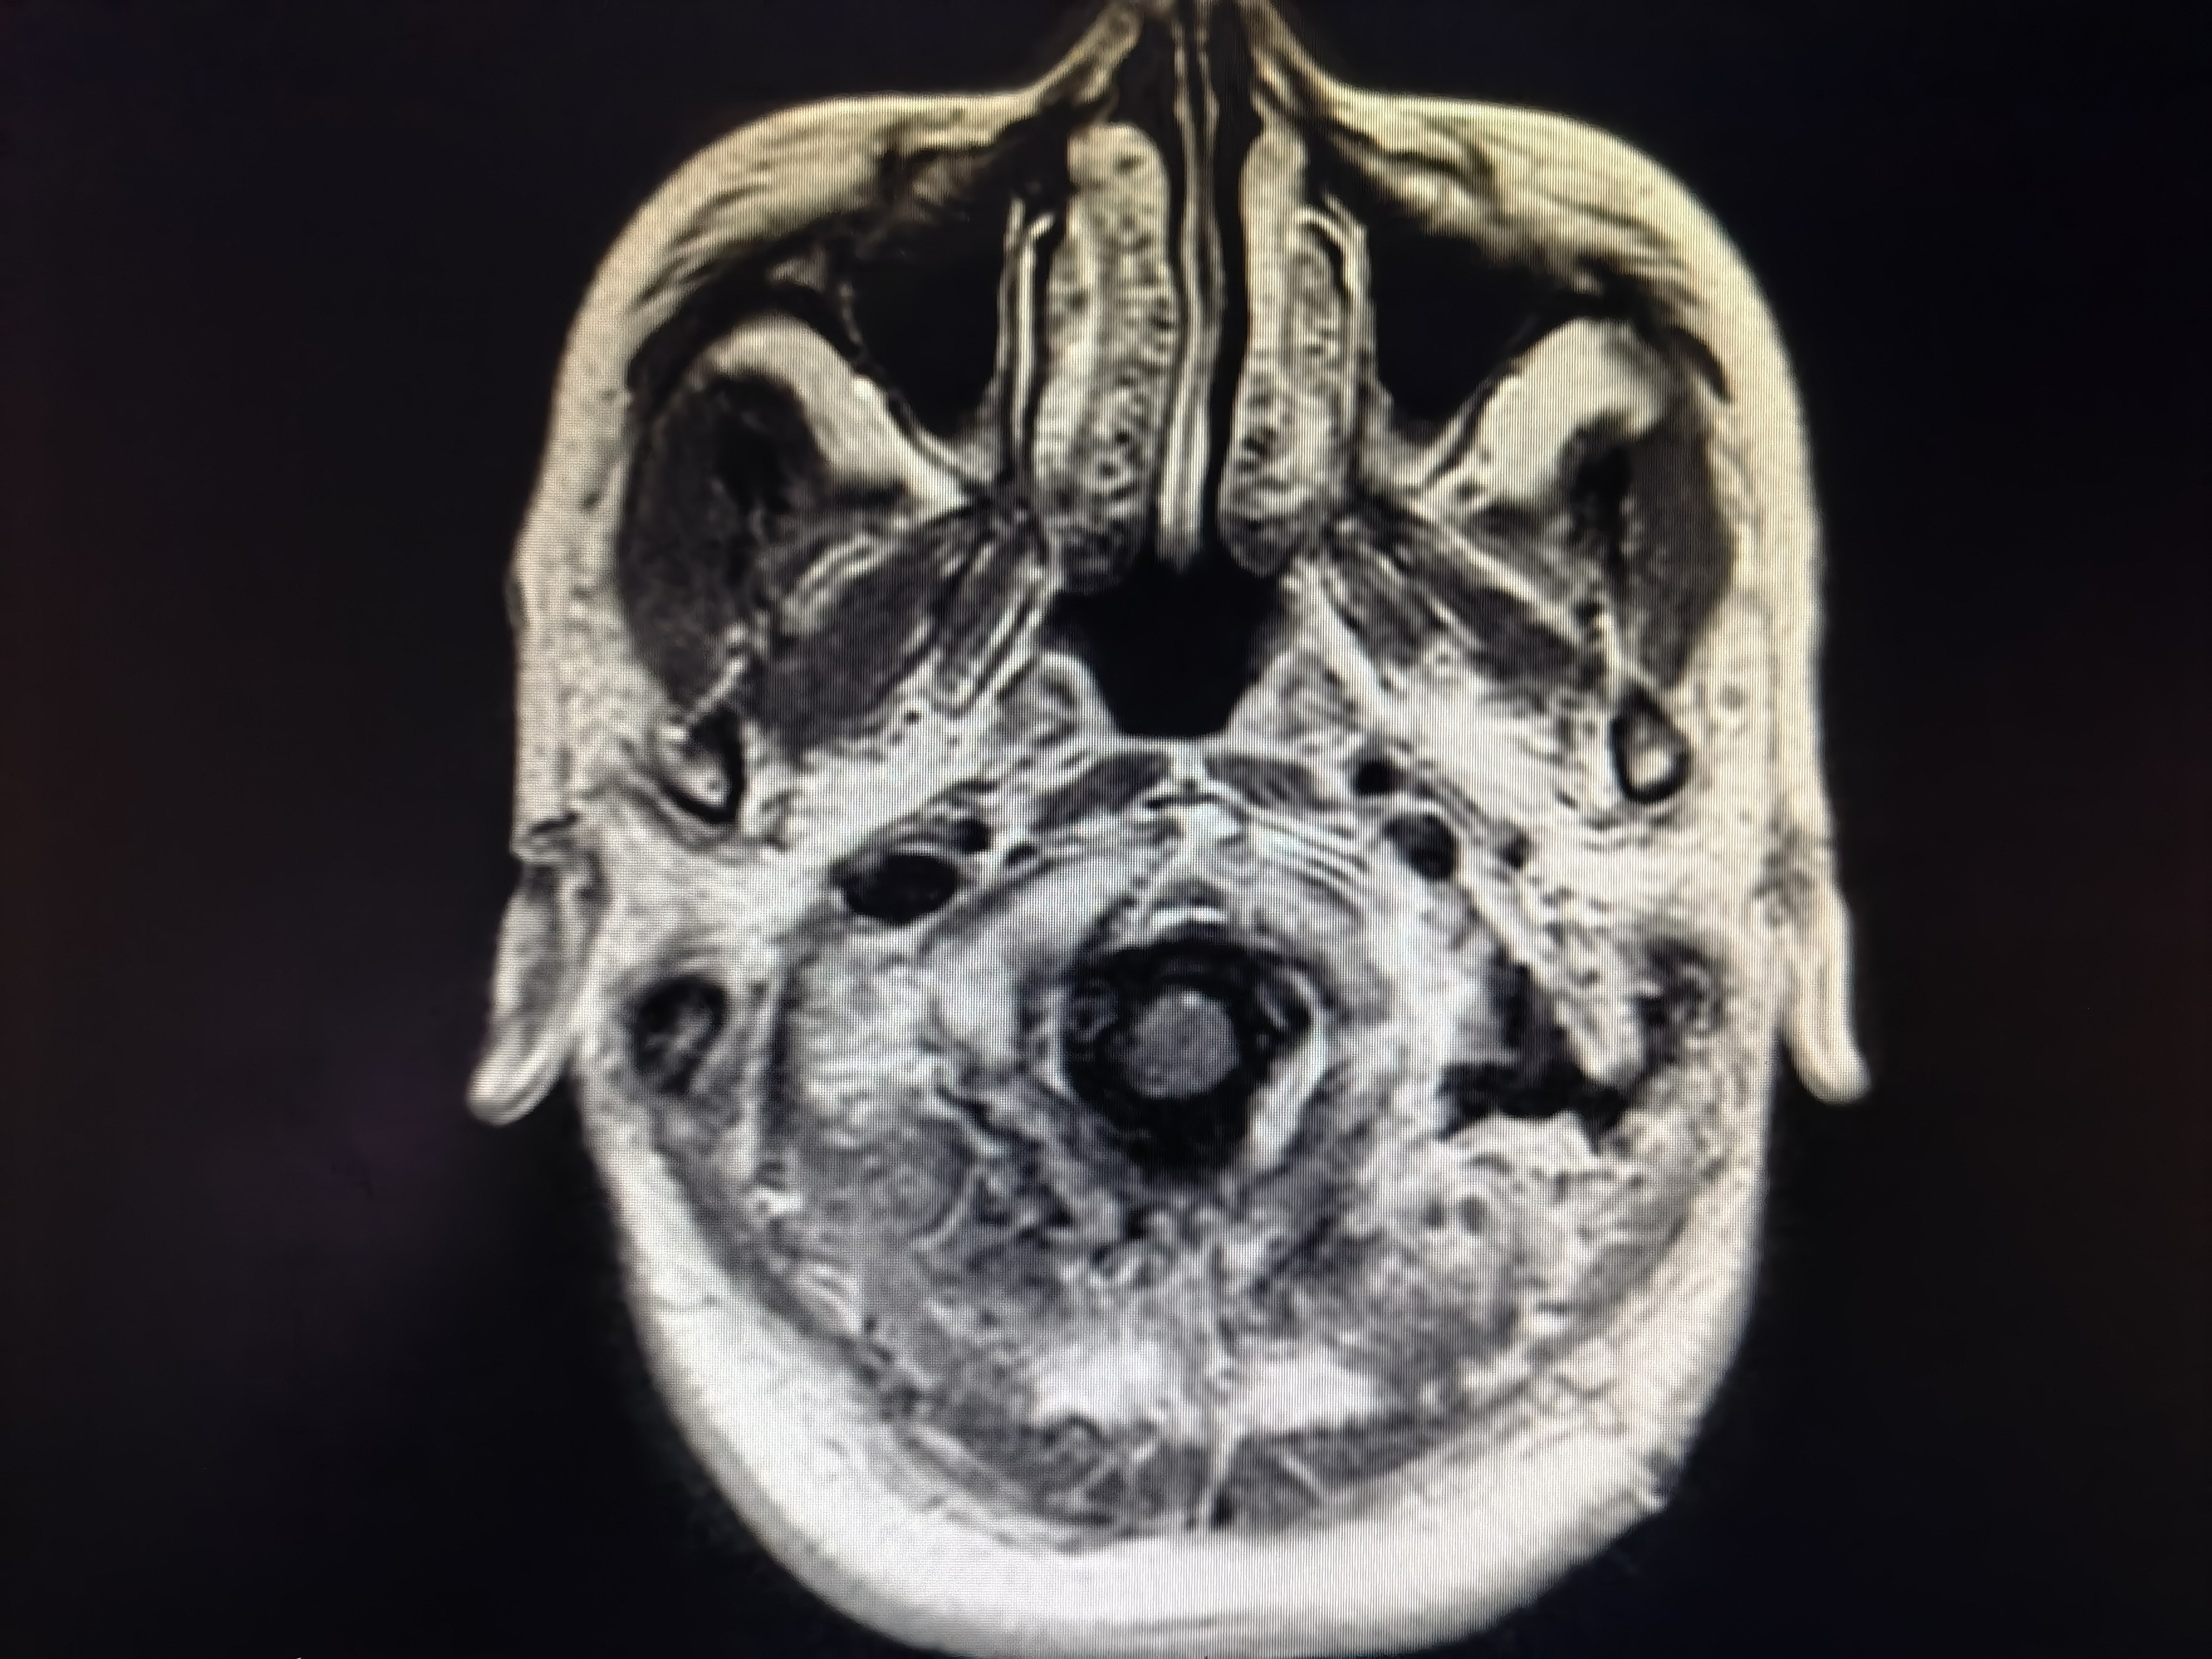

术前磁共振